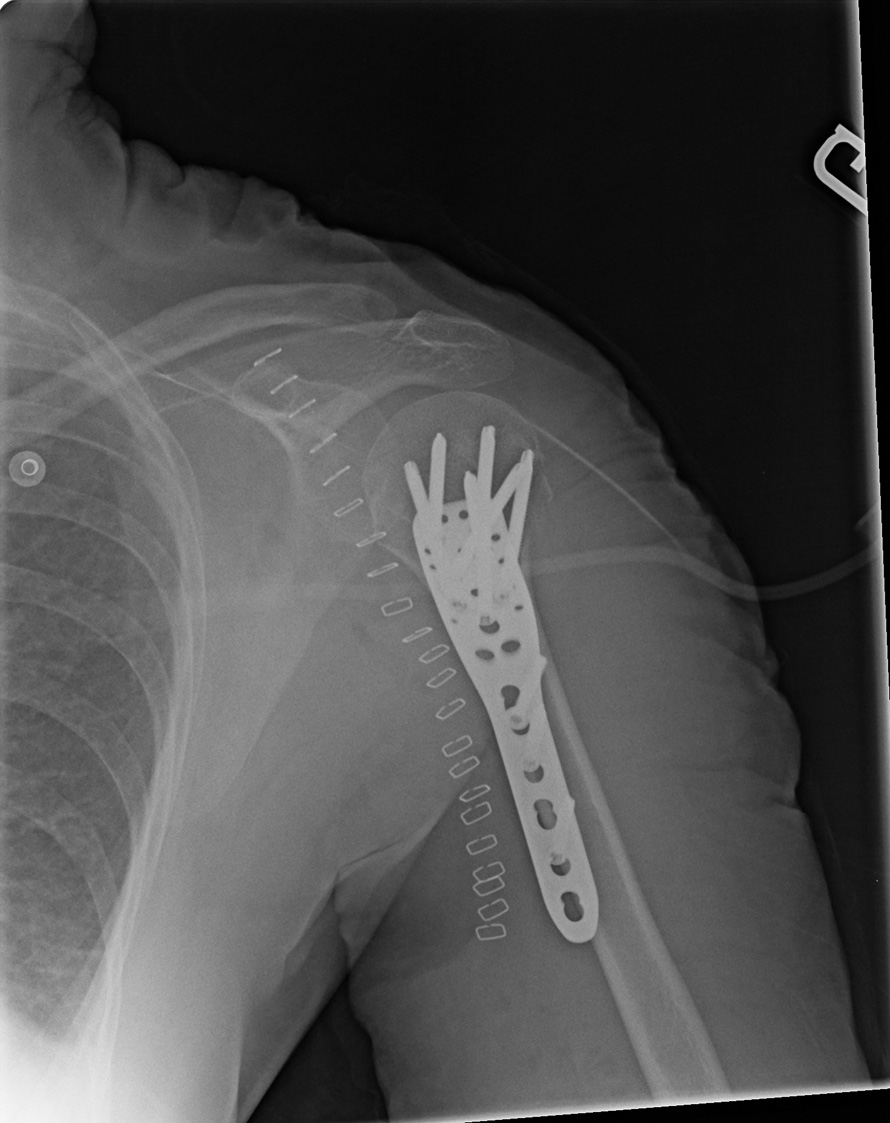

62-year-old female:

Shoulder pain following a fall from standing height on a hyperextended arm.

Philos plate

Proximal humerus fracture

Plate and screws

Open reduction of a proximal humerus fracture and internal fixation with a Philos plate. Multiple screws provide enhanced stability.

Metallic staples

Metallic staples for skin closure.

Anteroposterior (internal rotation)

• Anteroposterior (internal rotation)